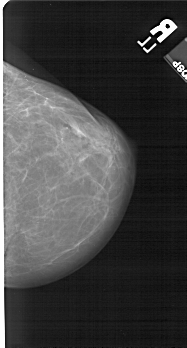

A_1524_1.RIGHT_CC

RIGHT_CC LINES 5206 PIXELS_PER_LINE 2791 BITS_PER_PIXEL 12 RESOLUTION 43.5 NON_OVERLAY